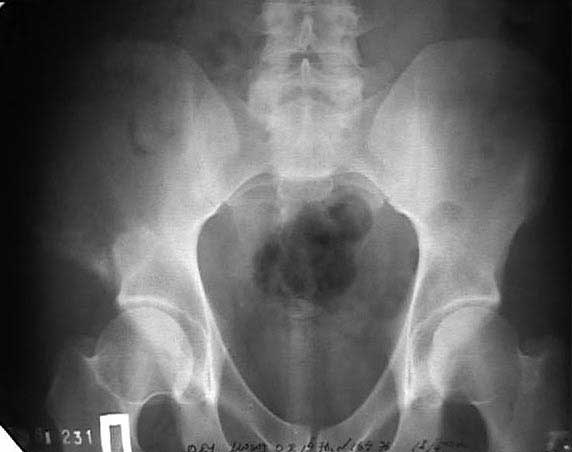

Могу пока выложить еще снимки и показать хронологию данного процесса и его прогрессирование, первый снимок был 2011 года. Вот этот 2009